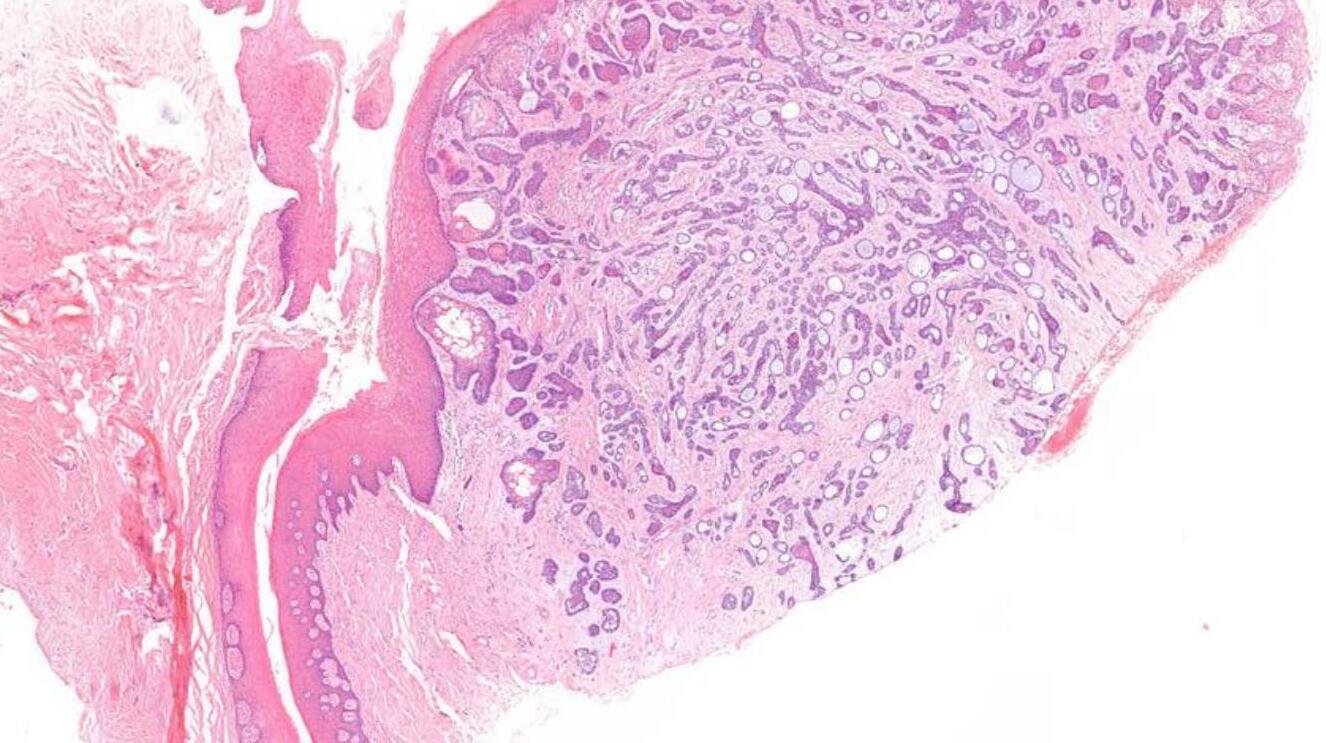

26-year-old, Female, Parotid tumour

Case 1- Salient points • Circumscribed salivary tumour, infiltrative periphery • Papillary cystic, microcystic patterns, hobnailing • Solid sheets of large polygonal cells with granular eosinophilic cytoplasm and vesicular nuclei • Secretory material –colloid-like eosinophilic secretions • Occasional mitotic figures • Work up? PAS, DPAS, • CK7, S100, DOG1, Mammoglobin

Secretory carcinoma

Discussion Differential diagnoses • Acinic cell carcinoma • Secretory carcinoma (previously called MASC) • MEC • 90% -ETV6::NTRK3 fusion -chromosomal rearrangement, t(12;15) (p13;q25) • ETV6::RET, ETV6::MET, ETV6::MAML3 • ETV6 translocation-negative secretory carcinoma. • Similar to Acinic cell carcinoma • But S100+, Mammoglobin+, DOG1-

5th ed Essential and desirable diagnostic criteria • Essential: single cell type with vacuolated colloid-like secretory material; no zymogen cytoplasmic granules; IHC positivity for S100 protein, SOX10, and mammaglobin; lack of IHC staining for p40 and/or p63 • Desirable: ETV6 or RET rearrangement demonstrated by FISH, RNA sequencing, or PCR • Low grade • Lymph node metastases are reported in as many as 25% of cases